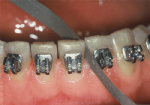

- Erschwerte Mundhygiene

Durch geeignete Putztechnik (spezielle Bürstchen) ist die Reinigung der Zähne trotzdem sehr gut möglich; das Gerät selbst schädigt den Zahnschmelz nicht und: ein sauberer Zahn wird nicht von Karies befallen! - Irritation der Mundschleimhaut zu Beginn der Behandlung